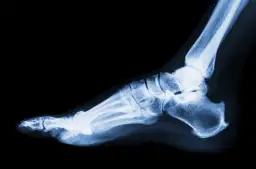

W przypadku, gdy skręcenie kostki jest powiązane z złamanie, konieczne jest natychmiastowe leczenie, aby zapobiec długotrwałym problemom zdrowotnym. Wczesna interwencja medyczna znacznie zwiększa szanse na szybki i pełny powrót do zdrowia.